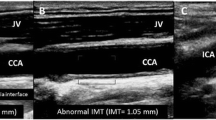

Surrogate Measures of Coronary Plaques

Flow-mediated dilatation is a test to measure endothelial dysfunction and thus a surrogate measure of coronary atherosclerosis. The endothelial dysfunction is measured in the brachial artery using ultrasound. Patients with PAD are known to manifest atherosclerosis, and as endothelial dysfunction is an early hallmark of atherosclerosis, it should be expected that flow-mediated dilation would be attenuated in all patients with PAD. This was demonstrated in a study of 44 patients with PAD but without symptoms of coronary artery disease [26]. In addition, the authors found that the degree of flow-mediated dilatation could predict the presence of ischemia on myocardial perfusion imaging. Thus far, these intriguing results have not been validated by other studies.

Coronary angiography by CT (CCTA) is a non-invasive method using intravenous contrast, typically to assess luminal stenoses. However, it has been shown that CCTA can also provide images of the vessel wall, and thus plaque characteristics, including positive remodeling, densitometry, and calcification [32]. With improved resolution, even small plaques that are not flow-limiting may potentially be assessed for vulnerability characteristics, although the spatial resolution remains a limitation for direct identification of vulnerable plaques [32]. Another challenge for CCTA is the fact that atherosclerosis is a systemic disease typically involving large parts of the coronary arteries. A comprehensive evaluation of coronary plaque morphology by visual evaluation is a cumbersome task. Multisequence magnetic resonance imaging (MRI) is also able to image the coronary artery wall and plaque morphology [33]., This method is even more technically challenging, however, due to cardiac and respiratory motion of the often small tortuous vessels. MRI does appear to be useful for imaging the larger carotid and aortic plaques.

O'Leary DH, Polak JF, Kronmal RA, Manolio TA, Burke GL, Wolfson Jr SK. Carotid-artery intima and media thickness as a risk factor for myocardial infarction and stroke in older adults. Cardiovascular Health Study Collaborative Research Group. N Engl J Med. 1999;340:14–22.